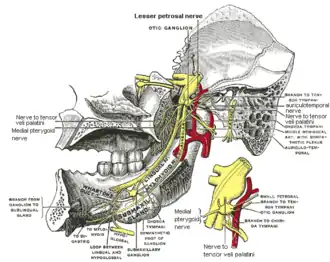

The otic ganglion and its branches. (Pterygoideus internus labeled at bottom right.) | |

Mandibular division of trifacial nerve, seen from the middle line.

Mandibular division of trifacial nerve, seen from the middle line. -